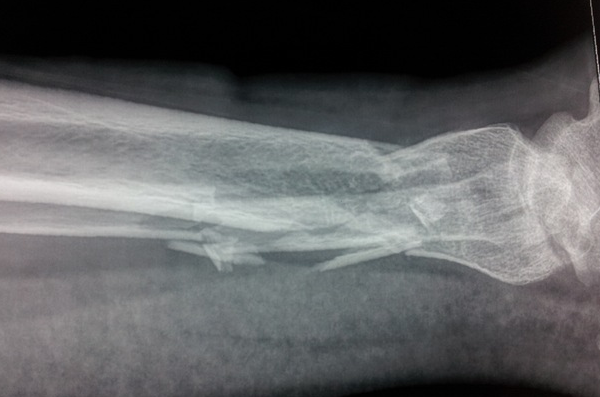

经过检查 , 小李的左手手臂骨折 , 而且患上了骨质疏松症 , 需要很长的时间才能恢复 , 很有可能影响到他的面试 。